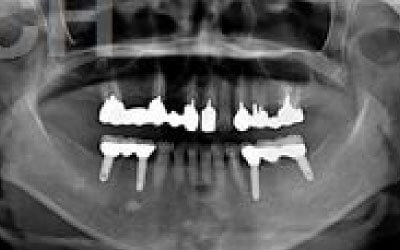

ブリッジとインプラントでは、前後の歯の寿命に大きな違いがあります。ブリッジでは、支えとなる歯を虫歯がなくても大きく削る必要があり、さらに噛む力が通常の1.5倍かかるため、その寿命が短くなりがちです。実際の統計によると、ブリッジの支えとなる歯の68%が、10年以内に抜歯を余儀なくされるという結果が出ています。

噛むとき、誰でも歯に何十キロもの力がかかっています。当然、歯の本数が減れば減るほど、残った歯にかかる負担は大きくなります。ブリッジ治療の場合、失われた歯にかかっていた力は、前後の歯で支えることになります。その結果、残った歯には、抜歯していないときに比べて1.5〜2倍程度の力がかかることになります。

ブリッジなどの治療では、前後の歯を大きく削る必要があります。場合によっては、虫歯がないのに歯の神経を取らなければならないこともあります。実際、神経を取って被せ物をすると、その歯は一気に「最終段階」に進んでしまうのです。しかし、インプラント治療では、前後の歯を削ることも、神経を取ることもありません。歯の寿命を延ばすためにも、健康な歯をできるだけ削らないことが非常に重要なのです。

最も大きな違いは、前後の歯の寿命に影響が出ることです。

ブリッジの場合、抜けた部分の前後の歯を大きな虫歯と同じくらい削る必要があります。

また、抜けた歯の力を前後の歯が支えているため、ブリッジを支える歯には常に1.5倍の負担がかかることになります。

1)ブリッジ

2)歯を大きく削る+支えの歯に1.5倍の力がかかる

3)前後の歯の寿命が著しく減る

ブリッジの支えの歯は、データでは10年以内に68%が抜歯になります。